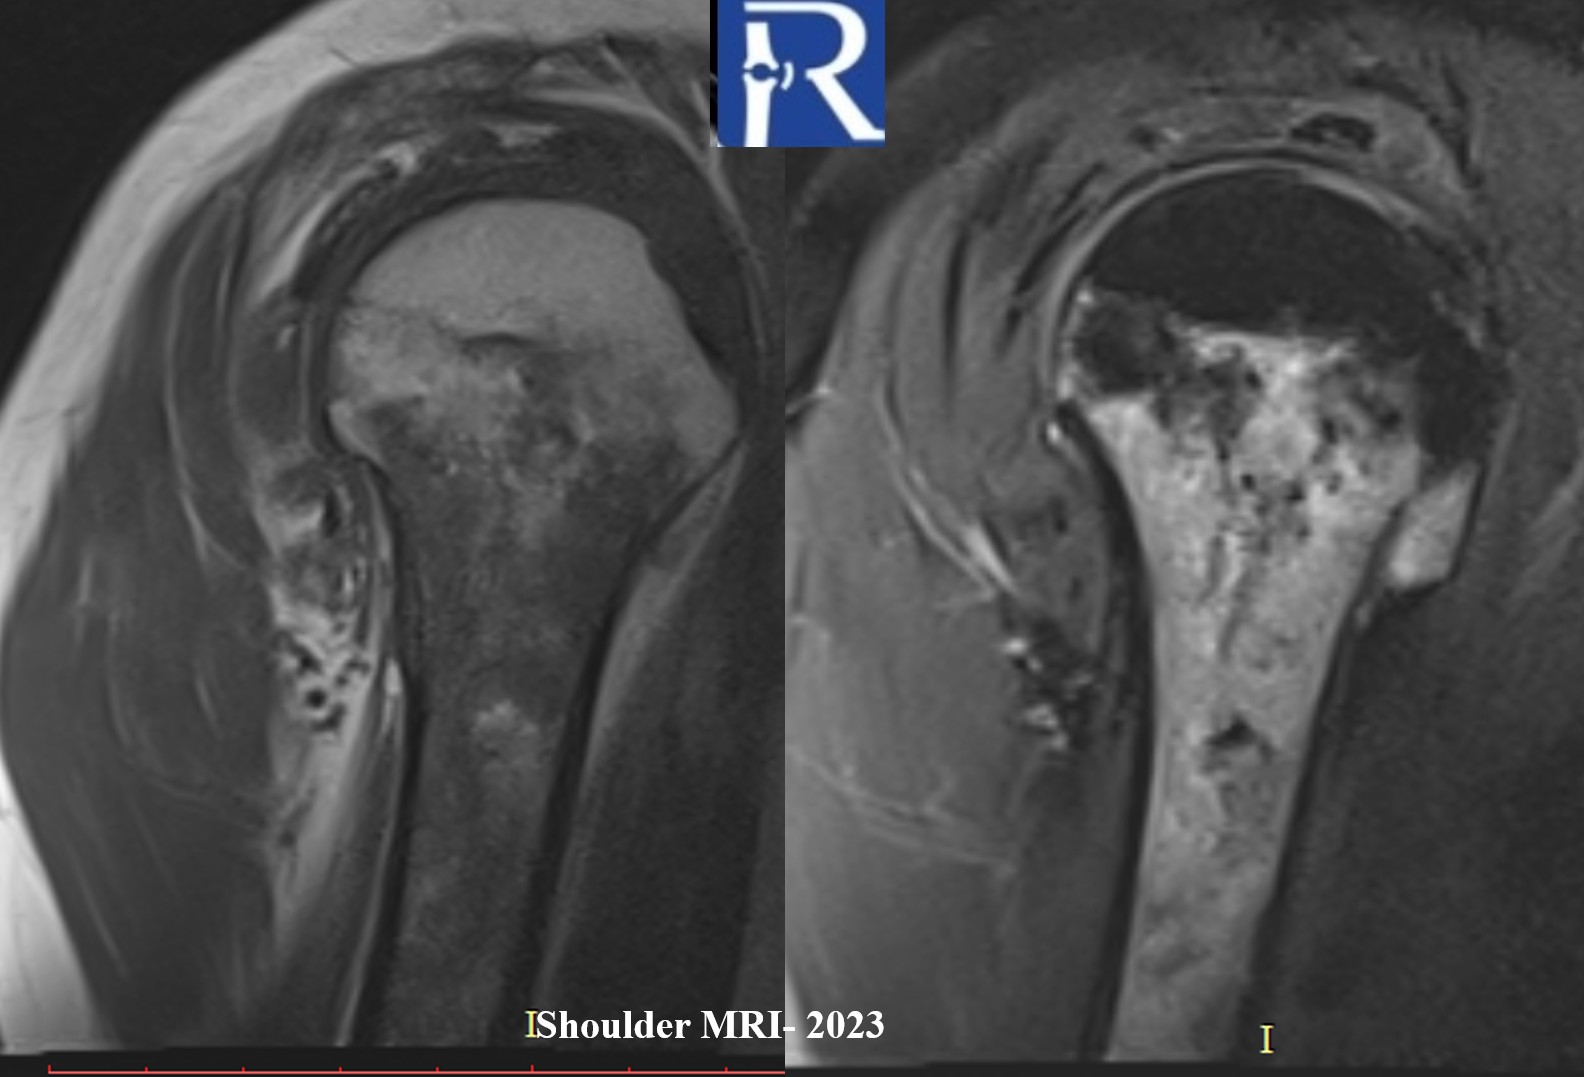

Magnetic Resonance Imaging (MRI)

- Retrospective review of a 2023 MRI revealed ill-defined heterogeneous bone marrow signal abnormalities consistent with bone marrow edema-like changes in the same region.